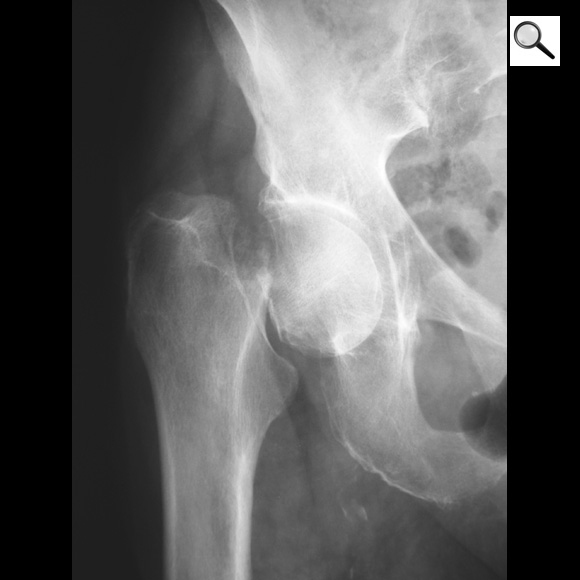

Q

Quel est le stade Garden de cette fracture de l’ES du fémur? Quel est le risque évolutif principal?

A

Fracture ES fémur garden 4 car perte de contact entre fragments,

les travées osseuses sont normales

Risque max d’ostéonécrose aseptique